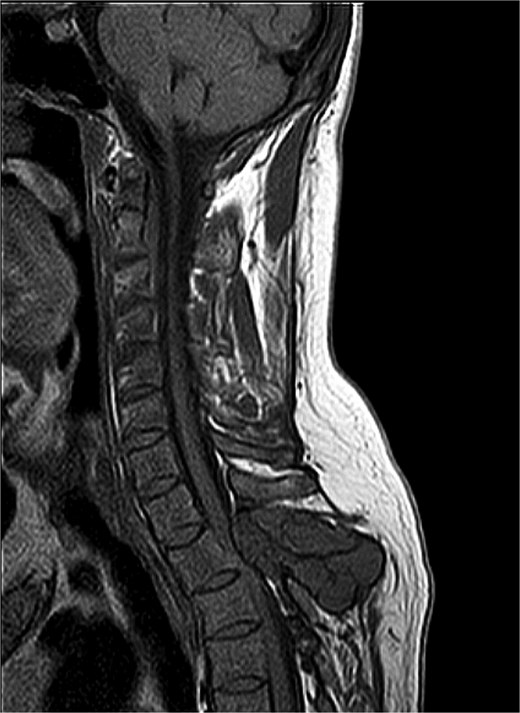

Magnetic resonance imaging (MRI) of the thoracic spine showed two expansile extradural lobulated lesions, the first of which involved the spinous process of the T2 vertebra with few hypointense non-enhancing septations within, anteriorly extending into the epidural space with narrowing of the spinal canal causing compression of the spinal cord with myelomalacic changes. A similar expansile lesion involving the right pedicle and lamina of the T3 vertebra and posterior aspect of the left T2 rib (Fig. 1). Parathyroid hormone was elevated at 713.6 pg/mL, Calcium was low at 2 mmol/L, phosphorus within normal limits at 1.10 mmol/L, while Alkaline phosphatase (ALP) was also elevated at 181 U/L (Table 1). Histopathological examination revealed spindle-shaped fibroblasts admixed with giant-cell-like osteoclasts, with areas of haemorrhage, and intracellular and stromal hemosiderin deposits. There were no mitoses or nuclear polymorphisms. A Tc-99 m sestamibi single-photon emission computed tomography/computed tomography (SPECT/CT) revealed soft tissue lesions inferior to lower poles of both thyroid lobes, the largest being 0.9 × 0.7 cm, suggestive of bilateral inferior parathyroid hyperplasia, without significant radiotracer uptake. Absence of significant tracer uptake is consistent with hyperplasia, where the glands are typically smaller and less rich in mitochondria-containing oxyphil cells as compared to adenomas [5].

MRI thoracic spine: Extradural lobulated minimally enhancing lesions involving spinous process of T2 vertebra, right pedicle and lamina of T3 vertebra and posterior aspect of left T2 rib.